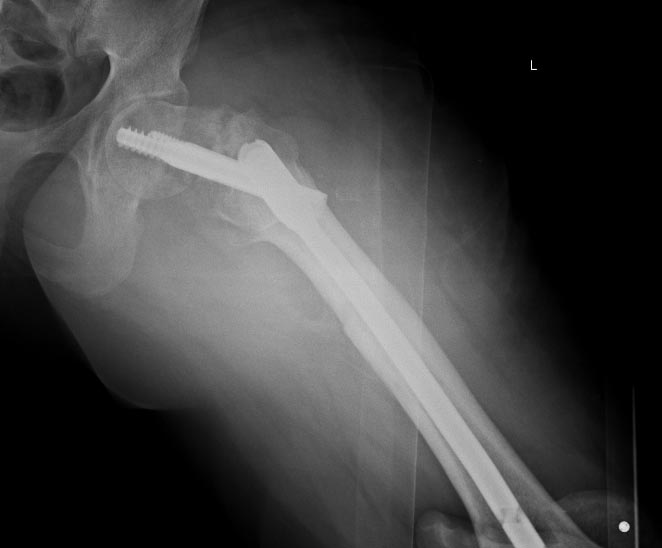

Сегодня сделали левое бедро. Сделана аналогичная чрескожная

вальгизирующая остеотомия, закрытый интрамедуллярный остеосинтез

Affixus.  Длинным, с учетом еще и бывшего диафизарного перелома. Были

какие-то мысли насчет пластики дефекта шейки - решили воздержаться.